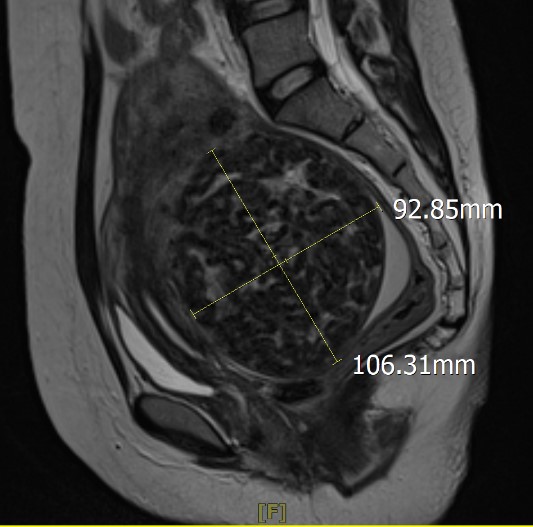

Fibroids are non-cancerous growths that develop in or on the uterus. They are common in women of reproductive age and can vary in size.